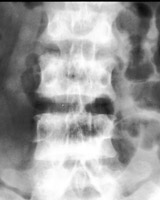

Roentgenographic appearance of increased density in the upper and lower zones of the vertebral body in a striated appearance. The pattern was similar to the alternating colors of the rugby player’s jersey design popular at the time of the description of this entity. Rugger Jersey spine is typically reserved for secondary hyperparathyroidism.

- Click on the image for a larger versionA - Click on the image for a larger versionB